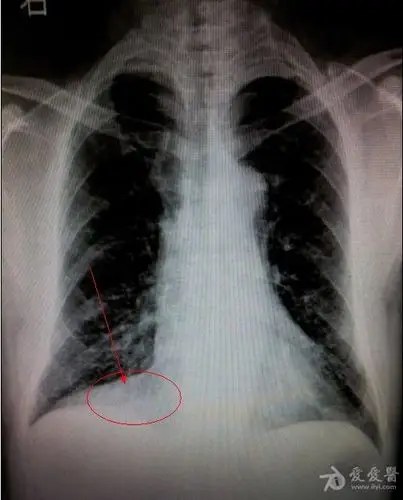

注意右侧心膈角,右下叶不张 的诊断成立.影像科的大夫会看图说话

右肺心膈角处囊性病变.请各位老师看看.

【影像读片】胆石症行腹部ct扫描发现右侧心膈角病灶,请您会诊.

增强 ct 示前心膈肿块,边界清楚(红色箭头).